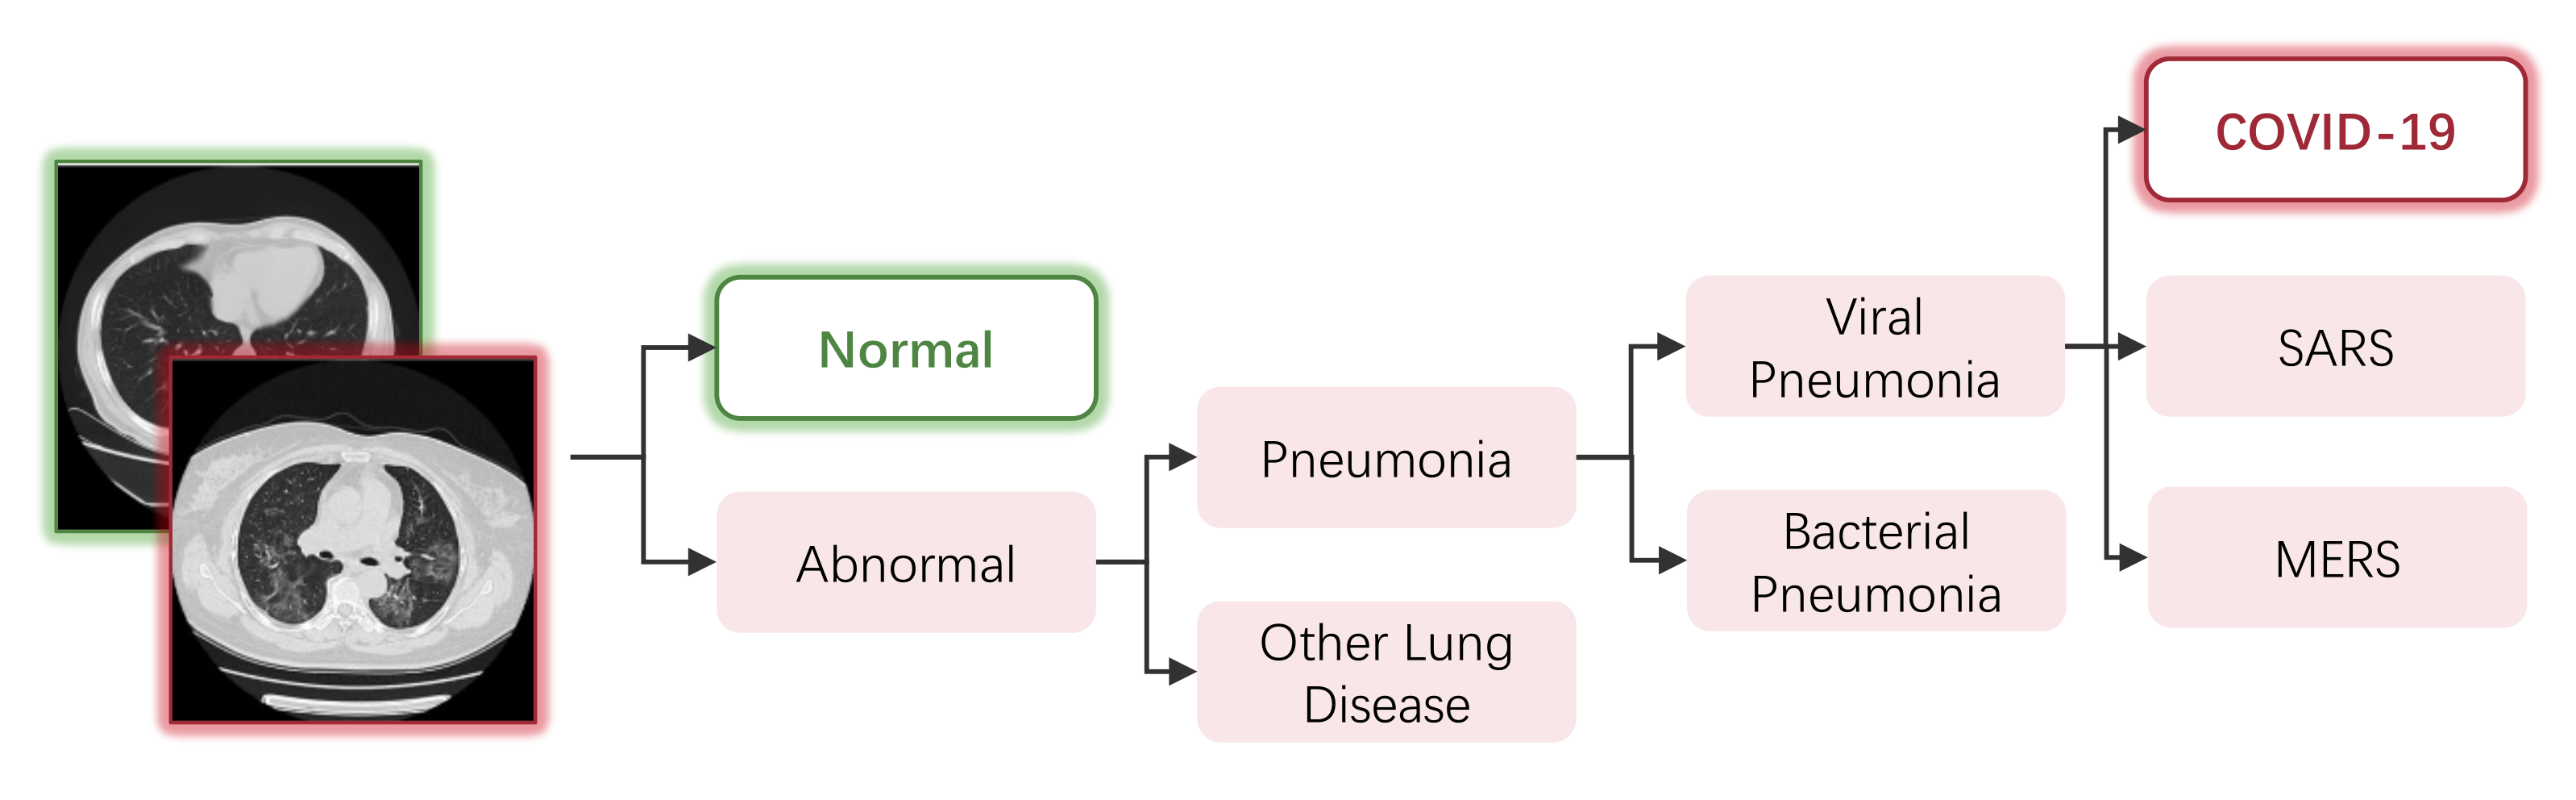

3. Automated Diagnosis of COVID-19

3.1. Image-Level Diagnosis: Classification-Based Models

3.1.1. Overview

3.2. Pixel-Level Diagnosis: Segmentation-Based Models

3.2.1. Overview